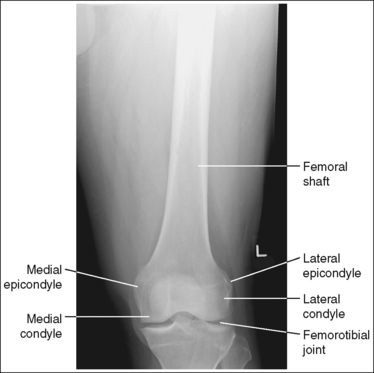

The knee demonstrates an AP projection. The medial and lateral femoral epicondyles are in profile, the femoral condyles are symmetrical, the intercondylar eminence is centered within the intercondylar fossa, and the tibia is superimposed over 0.25 inch (0.6 cm) of the fibular head.

• To obtain an AP knee projection, place the patient in a supine position with the knee fully extended. Internally rotate the leg until an imaginary line drawn between the medial and lateral femoral epicondyles is positioned parallel with the IR (Figure 6-71). This positioning places the medial and lateral femoral epicondyles at equal distances from the IR as well as medially and laterally in profile, respectively. It also centers the intercondylar eminence within the intercondylar fossa and draws the fibular neck and a portion of the fibular head from beneath the tibia.

• Effect of rotation. If the femoral epicondyles are not positioned parallel with the IR, an AP projection has not been obtained. If the patient's leg was not internally rotated enough to place the epicondyles at equal distances from the IR, they are not in profile, the medial femoral condyle appears larger than the lateral condyle, and the tibia is superimposed over more than 0.25 inch (0.6 cm) of the fibular head (see Image 54). If the patient's leg was internally rotated more than needed to place the femoral epicondyles at equal distances from the IR, the epicondyles are not demonstrated in profile, the lateral femoral condyle appears larger than the medial condyle, and the tibia is superimposed over less than 0.25 inch (0.6 cm) of the fibular head (see Image 55).

The knee joint space is open, the anterior and posterior condylar margins of the tibia are superimposed, the intercondylar eminence and tubercles are demonstrated in profile, and the fibular head is demonstrated approximately 0.5 inch (1.25 cm) distal to the tibial plateau.

• The anterior and posterior condylar margins of the tibia are superimposed if the correct central ray angulation, as determined by the patient's upper thigh and buttocks thickness, is used. By studying the tibial plateau region, you will see that the tibial plateau slopes distally approximately 5 degrees from the anterior condylar margin to the posterior condylar margin on both the medial and lateral aspects (Figure 6-72). Only if the central ray is aligned parallel with the tibial plateau slope is an open knee joint space obtained.

• Center the central ray to the midline of the knee at a level 1 inch (2.5 cm) distal to the palpable medial epicondyle to place the knee joint in the center of the exposure field. (As long as the knee remains extended, an alternative central ray placement is 0.5 inch (1.25 cm) distal to the patellar apex.) Open the longitudinal collimation enough to include one fourth of the distal femur and proximal lower leg. Transverse collimation should be to within 0.5 inch (1.25 cm) of the knee skin line.

The femoral epicondyles are not in profile, the medial femoral condyle appears larger than the lateral condyle, and the fibular head demonstrates more than 0.25 inch (0.6 cm) of tibial superimposition. The leg was externally rotated.

Internally rotate the leg until the femoral epicondyles are at equal distances from the IR.

The femoral epicondyles are not in profile, the lateral femoral condyle appears larger than the medial condyle, and the fibular head demonstrates less than 0.25 inch (0.6 cm) of tibial superimposition. The leg was internally rotated.

Externally rotate the leg until the femoral epicondyles are at equal distances from the film.